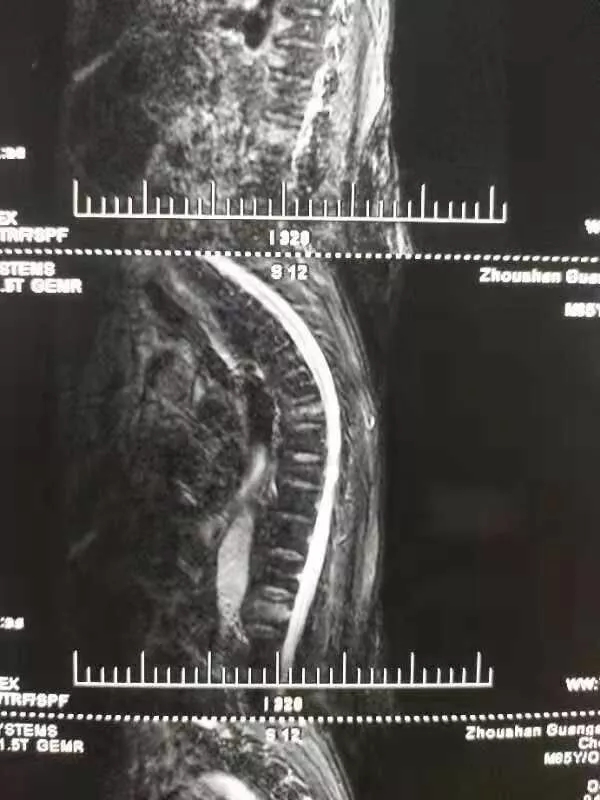

陳爺爺23日被家人送到我院門診,門診MRI、X片等檢查后,檢查結果為“腰1椎椎體壓縮性骨折”,門診在對癥處理后以“腰1椎體壓縮性骨折”將老人收入脊柱科。

進行完善的檢查,脊柱科對老人病情確診如下:胸7、腰1椎體壓縮性骨折,重度骨質疏松癥。